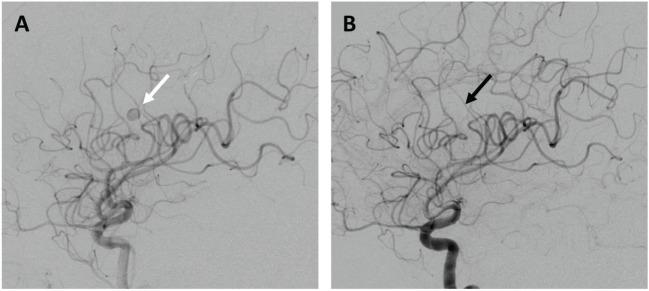

Penetrating brain trauma commonly results in occult neurovascular injury. Detailed cerebrovascular imaging can evaluate the relationship of intracranial foreign bodies to major vascular structures, assess for traumatic pseudoaneurysms, and ensure hemostasis during surgical removal. We report a case of a self-inflicted intracranial nail gun injury causing a communicating ventricular tract hemorrhage upon removal, as well as a delayed pseudoaneurysm. Pre- and post-operative vascular imaging, as well as intra-operative endovascular assistance, was critical to successful foreign body removal in this patient. This report demonstrates the utility of endovascular techniques for the assessment and treatment of occult cerebrovascular injuries from intracranial foreign bodies.

穿透性脑外伤常导致隐匿性神经血管损伤。详细的脑血管成像可评估颅内异物与主要血管结构的关系,检测创伤性假性动脉瘤,并确保手术取出异物时的止血效果。我们报告一例自伤性颅内钉枪伤病例,取出异物时导致交通性脑室系统出血以及迟发性假性动脉瘤。术前和术后血管成像以及术中血管内辅助对该患者成功取出异物至关重要。本报告证明了血管内技术在评估和治疗颅内异物所致隐匿性脑血管损伤中的作用。